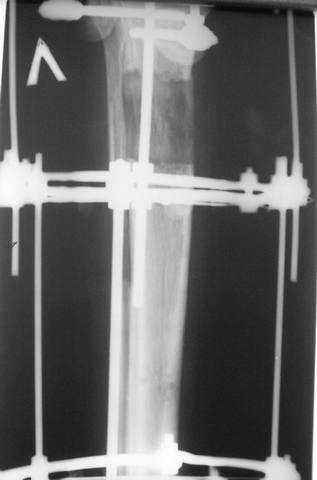

3,4 - через 4 недели наложен спице-стержневой аппарат, произведена остеотомия большеберцовой кости в верхней трети, раны зажили, проводилась дистракция в аппарате.